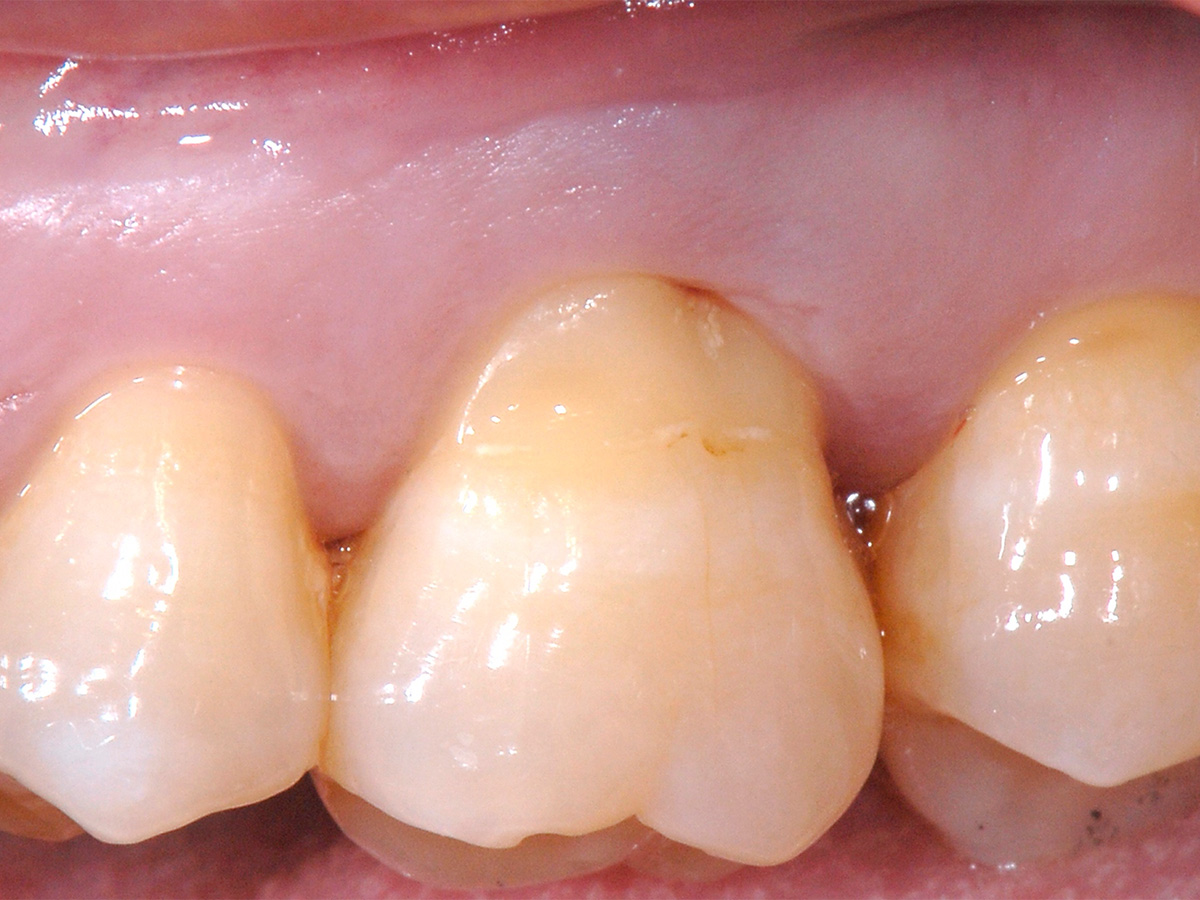

Abbildung 12

Klinische Situation des Zahnes 26 zum Zeitpunkt der Nachsorge nach drei Monaten.